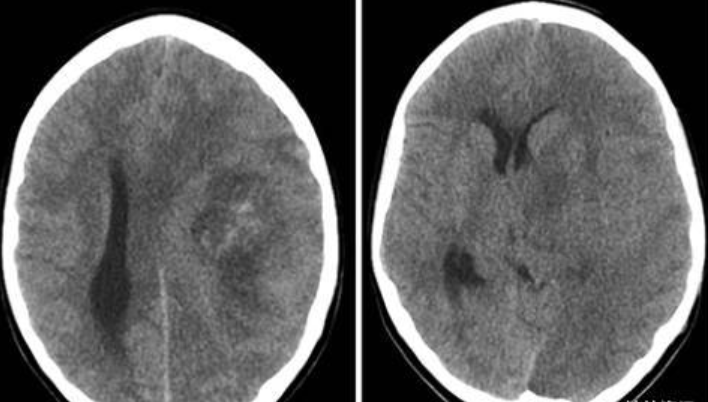

胶质瘤术后癫痫是怎么回事?胶质瘤术后癫痫,一是要看患者术前是否有癫痫,脑胶质瘤本身也会引起局部的刺激、神经元的异常放电也会引起癫痫发作。一些癫痫发作会在手术后消失,但一些病人在术后癫痫还会继续发作。

二是如果病人手术前没有发生过癫痫,术后不久便产生了癫痫,这可能是由于手术切除肿瘤后,产生并发症,局部病灶水肿、出血导致的。如果是术后几个月才出现的癫痫,这是因为切除肿瘤的脑区形成了瘢痕,瘢痕(scar)是各种创伤后所引起的正常皮肤组织的外观形态和组织病理学改变的统称,它是人体创伤修复过程中必然的产物。随着瘢痕的增生,也会导致出现癫痫。

其实对于大多数胶质瘤术后癫痫患者来说,其手术后还有癫痫的根本原因是手术切除率不高,胶质瘤术后残留比较多。二是胶质瘤手术过程中,手术创伤过大,在人体创伤修复过程中就会产生更多的瘢痕,其产生癫痫的概率更大。